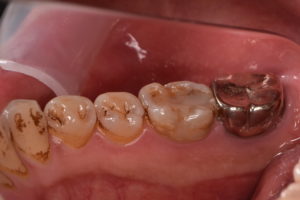

歯冠修復後

ジルコニアセラミッククラウン 132,000円(支台築造、仮歯代含む)

また根管治療後に適合の良い、再感染の起こりにくいジルコニアセラミッククラウンでしっかり再感染を防ぐことが根管治療の予後を左右します。

根管治療とともに歯冠修復物の精度がその歯の予後にとって極めて重要であると言えます。

根管治療と歯冠修復物の精度を高めるために当院ではマイクロスコープや高倍率ルーペを使用しています。